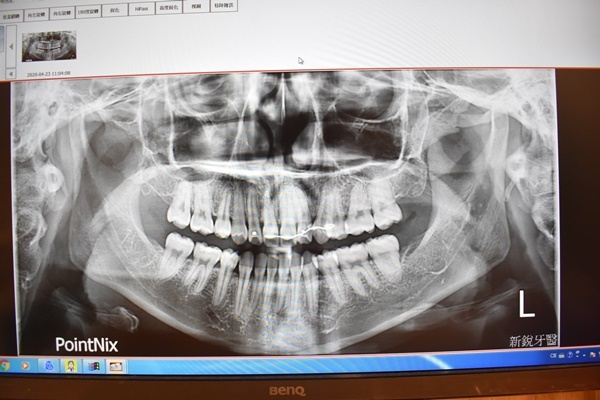

護士先跟我約了時間拍攝全口斷層掃瞄取資料以及咬模